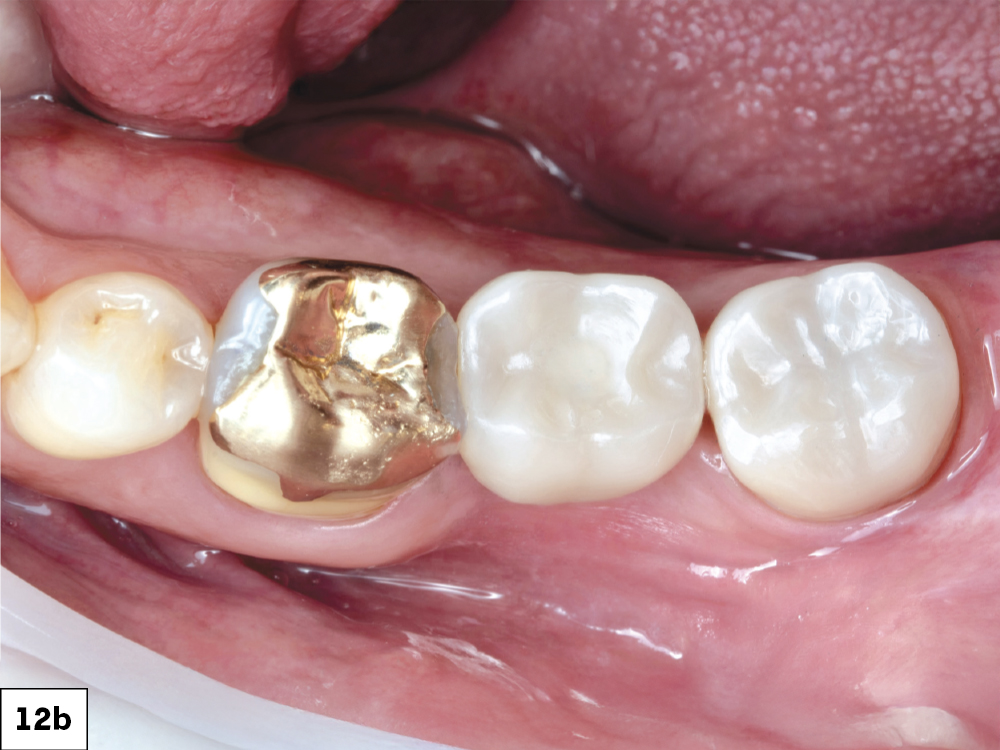

BruxZir NOW SRC in mouth with open access channel

BruxZir NOW SRC in mouth with closed access channel

BruxZir NOW SRC in mouth radiograph

Figures 12a–12c: The screw-retained crown was seated and the access channel sealed with Teflon tape and composite. The final restoration showed ideal contacts, occlusion and emergence profile.